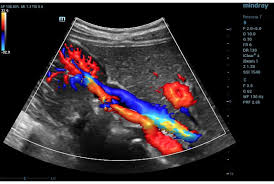

Color Doppler Ultrasound

A non-invasive test to assess blood flow in arteries and veins, detect blockages or circulation issues.